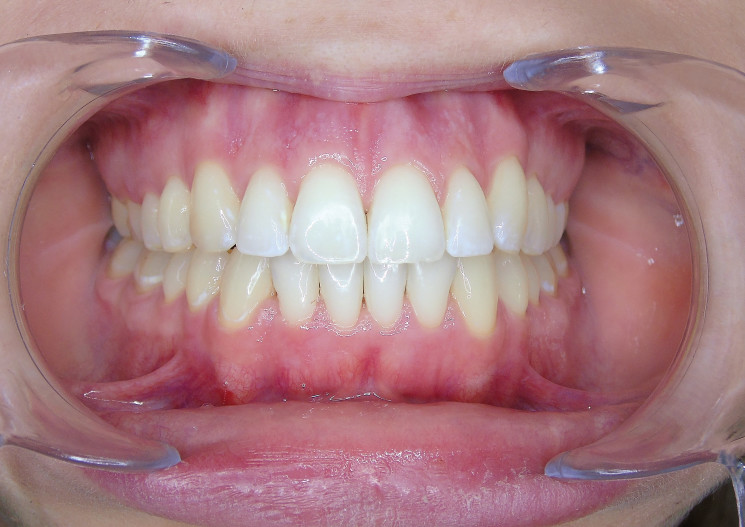

Der extraorale Befund (Abb. 1a–c) ergab ein gerades Durchschnittsgesicht mit leicht vergrößertem Nasolabialwinkel, ein symmetrisches Gesicht bei potenziell inkompetentem Lippenschluss sowie einen dolichofazialen Gesichtstyp. Intraoral lag beidseits annähernd eine Angle-Klasse I mit frontal offenem Biss (–2,5 mm) sowie ein dental-transversal zu schmaler Oberkiefer vor, woraus ein Kopfbiss von 13 und 23 resultierte. Des Weiteren zeigten sich ein persistierendes viszerales Schluckmuster und eine Inkongruenz der Kiefermitten (Abb. 2a–e; Abb. 3).

Durch sogenannte Optimized-Extrusion-Attachments wurde eine Extrusion der oberen Frontzähne von max. 2,3 mm und der unteren Frontzähne von max. 1,4 mm geplant (Abb. 4a–c). Mithilfe einer leichten Expansion der Prämolarenregion konnte der Platzmangel im Oberkiefer ohne ASR kompensiert werden.

Sechs Monate nach Abschluss der Therapie besteht weiterhin ein stabiles Ergebnis. Wie im Vergleichsbild (Abb. 5a–c) zu sehen ist, konnte die geplante vertikale Korrektur vollständig erzielt und die Mittellinie bis auf eine MLV von 1 mm nach rechts im UK korrigiert werden.

Somit kann gezeigt werden, dass auch ohne operativen Eingriff oder festsitzende Apparaturen in kürzester Zeit ein ästhetisch und funktionell zufriedenstellendes Ergebnis erzielt werden kann (Abb. 6a–c; Abb. 7a–e). Es wird daher nachvollziehbar dargestellt, dass bei entsprechender Indikation Aligner für die Behandlung frontal offener Bisse eine hervorragende Alternative zu den konventionellen Behandlungsmethoden sein können. Voraussetzung für diesen Therapieansatz ist ein motivierter Patient mit guter Compliance.